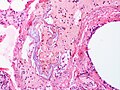

Microscopic (VTE)

Features:

- Layers consisting of platelets and fibrin alternating with layers of RBCs - known as Lines of Zahn.[7]

Note:

- Multiple laminations (layers), in general, suggest that clot was formed in a dynamic environment, i.e. in the context of blood flow.